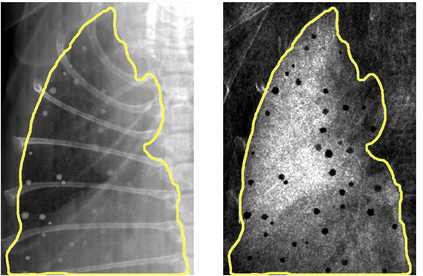

Low-dose computed tomography (LDCT) is the current standard for lung cancer screening, yet its adoption and accessibility remain limited. Many regions lack LDCT infrastructure, and even among those screened, early-stage cancer detection often yield false positives, as shown in the National Lung Screening Trial (NLST) with a sensitivity of 93.8 percent and a false-positive rate of 26.6 percent. We aim to investigate whether X-ray dark-field imaging (DFI) radiograph, a technique sensitive to small-angle scatter from alveolar microstructure and less susceptible to organ shadowing, can significantly improve early-stage lung tumor detection when coupled with deep-learning segmentation. Using paired attenuation (ATTN) and DFI radiograph images of euthanized mouse lungs, we generated realistic synthetic tumors with irregular boundaries and intensity profiles consistent with physical lung contrast. A U-Net segmentation network was trained on small patches using either ATTN, DFI, or a combination of ATTN and DFI channels.Results show that the DFI-only model achieved a true-positive detection rate of 83.7 percent, compared with 51 percent for ATTN-only, while maintaining comparable specificity (90.5 versus 92.9 percent). The combined ATTN and DFI input achieved 79.6 percent sensitivity and 97.6 percent specificity. In conclusion, DFI substantially improves early-tumor detectability in comparison to standard attenuation radiography and shows potential as an accessible, low-cost, low-dose alternative for pre-clinical or limited-resource screening where LDCT is unavailable.